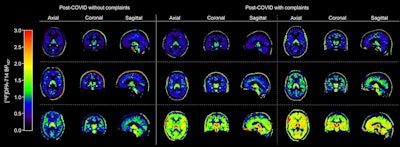

Examples of quantitative cerebral F-18 DPA-714 images of brain in post-COVID individuals. *Parametric Logan VT images corrected for K1/k2 (global cerebral region; gray and white matter) and subtracted by 1, creating indirect BPND images. VT = total distribution volume.Examples of quantitative cerebral F-18 DPA-714 images of brain in post-COVID individuals. *Parametric Logan VT images corrected for K1/k2 (global cerebral region; gray and white matter) and subtracted by 1, creating indirect BPND images. VT = total distribution volume.Journal of Nuclear Medicine“We found widespread elevated neuroinflammatory activity, as measured with TSPO-PET, in some post-COVID individuals with persistent severe fatigue and/or difficulty concentrating compared with individuals without these complaints,” the group wrote.

After adjusting for age, body mass index, and PET scanner type, the researchers found significantly higher binding in global gray matter in individuals with versus without persistent complaints (nondisplaceable binding potential, 0.8 ± 0.34 vs. 0.65 ± 0.17, p = 0.036). Additionally, while no significant differences in binding levels of the other regions were observed between groups, visual inspection showed similar high binding levels in the cerebellum in some with persistent complaints compared to those without complaints.